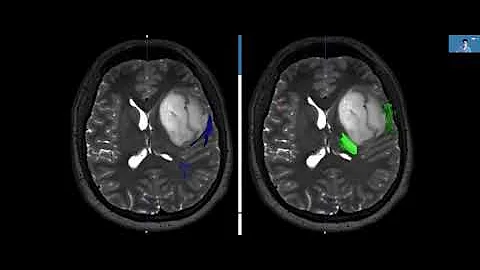

Overview Of Brain Tumors: Ucla Brain Tumor Virtual Conference '22

The UCLA Brain Tumor Center hosted a virtual meeting for patients and caregivers to offer lectures on treatments, diagnosis, ...